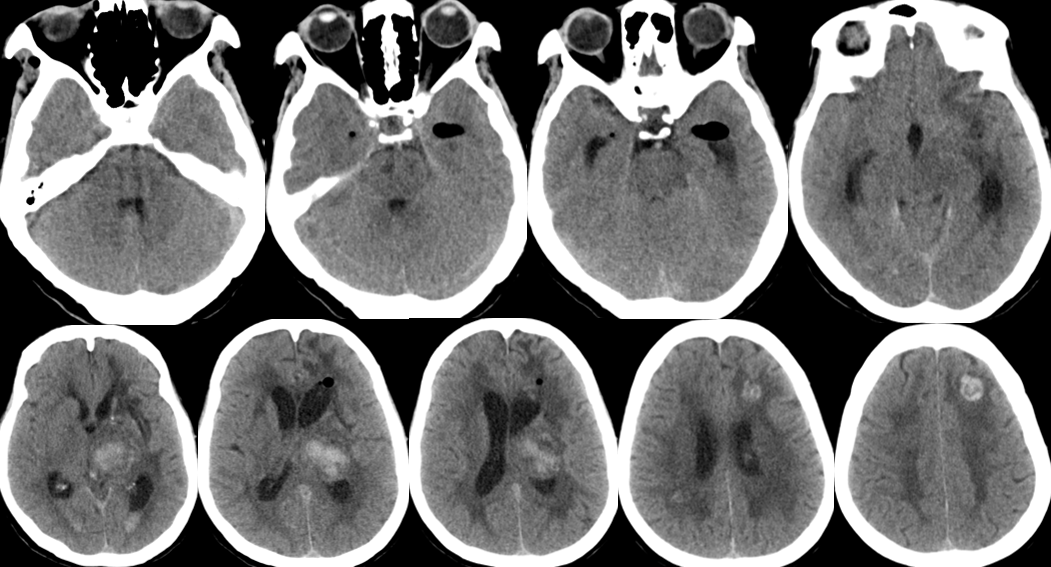

2014-11-18 0am CT

2014-11-18 10am CT

2014-11-19 CT

2014-11-20 CT

2014-11-24 CT

2014-11-18 CT

2014-11-27 CT

2014-12-2 CT